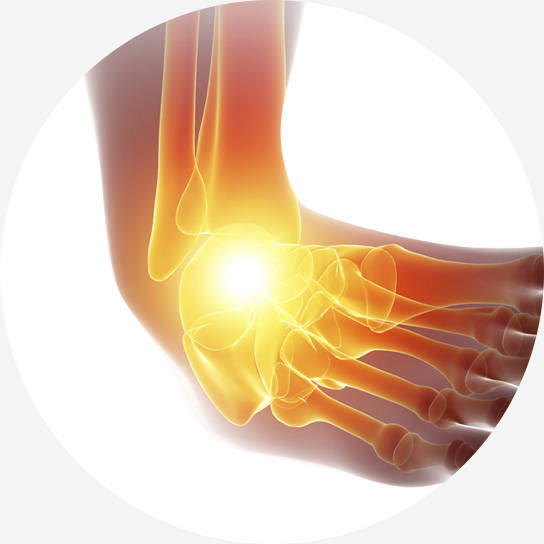

발목 인대는 발목 관절의 안정성을 유지하고, 발의 과도한 움직임을

제한하여 발목 관절을 보호하는 역할을 합니다.

걷거나 뛰는 등의 일상적인 활동을 가능하게 하고, 발목 관절의

정상적인 기능을 유지하는 데 필수적인 역할을 합니다.

발목을 접질리거나 회전 손상을 입는 경우 발생할 수 있으며, 스포츠 활동 중, 낙상, 교통사고 등 다양한 원인으로 발생할 수 있습니다.

활동량이 많을수록 더 많이 발생하는 발목 염좌는 초기 치료가 중요합니다.